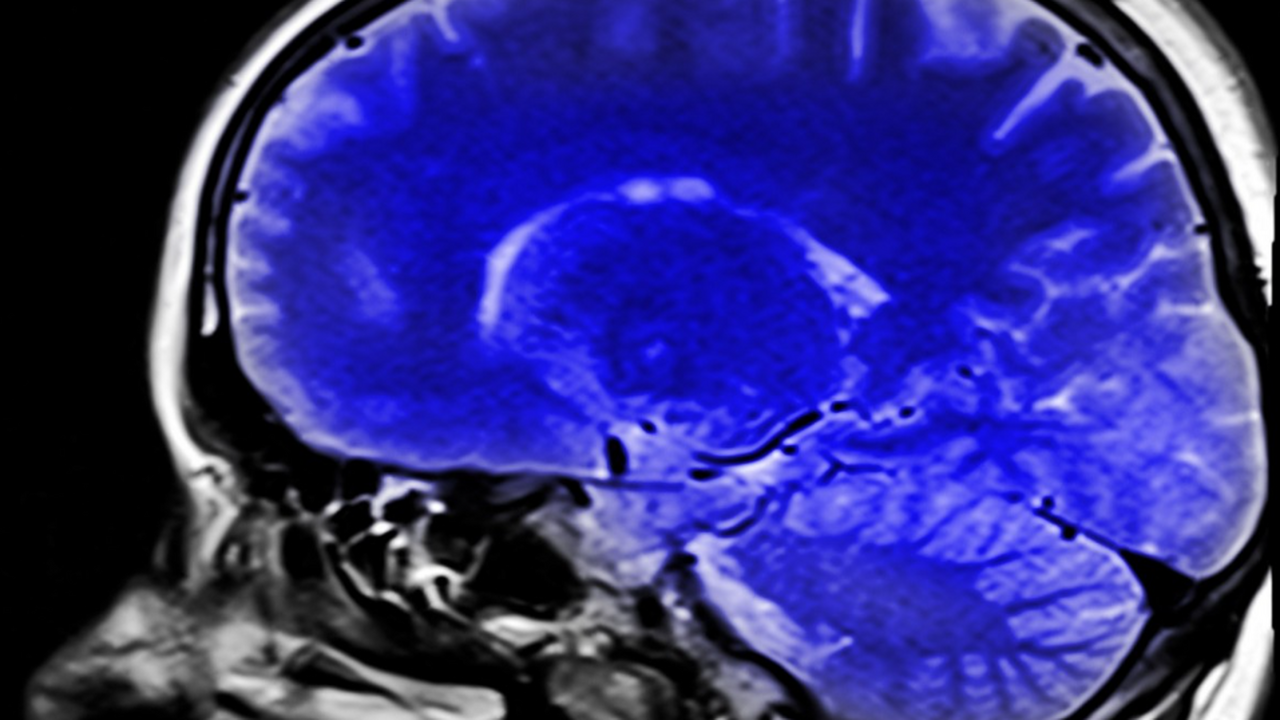

Как рассказал ТАСС вице-президент РАН Михаил Пирадов, такая установка представляет собой не привычный кремниевый чип, а небольшую пластиковую пластину, в которой сделаны тончайшие каналы. В них помещают выращенные в лаборатории клетки определённого органа – от мозга и сердца до лёгких или почек. Внутри каналов создают имитацию кровотока, благодаря чему клетки ведут себя почти так же, как в реальных тканях.

Главный научный потенциал этой технологии заключается в возможности оперативно оценивать, как лекарственные вещества проходят через естественные барьеры организма, включая гематоэнцефалический барьер, который защищает мозг. Это критически важно при изучении препаратов для лечения нейродегенеративных заболеваний.